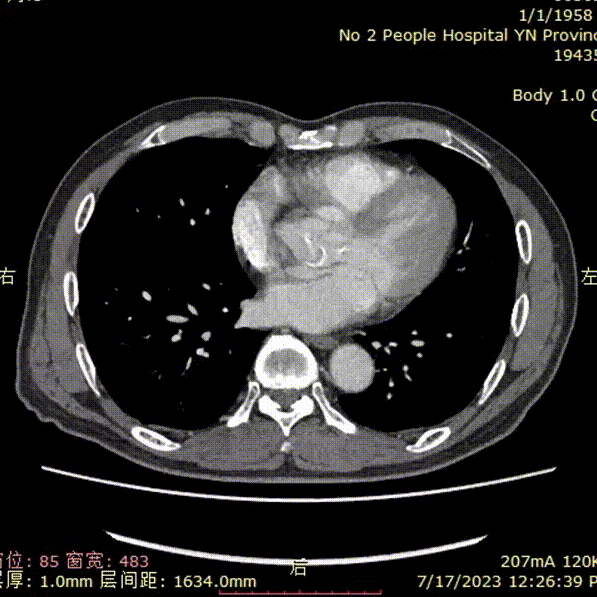

五、术后一周复查CT

术后一周复查:支架位置合适、形态良好,双侧髂内血供得以保留;无内漏。